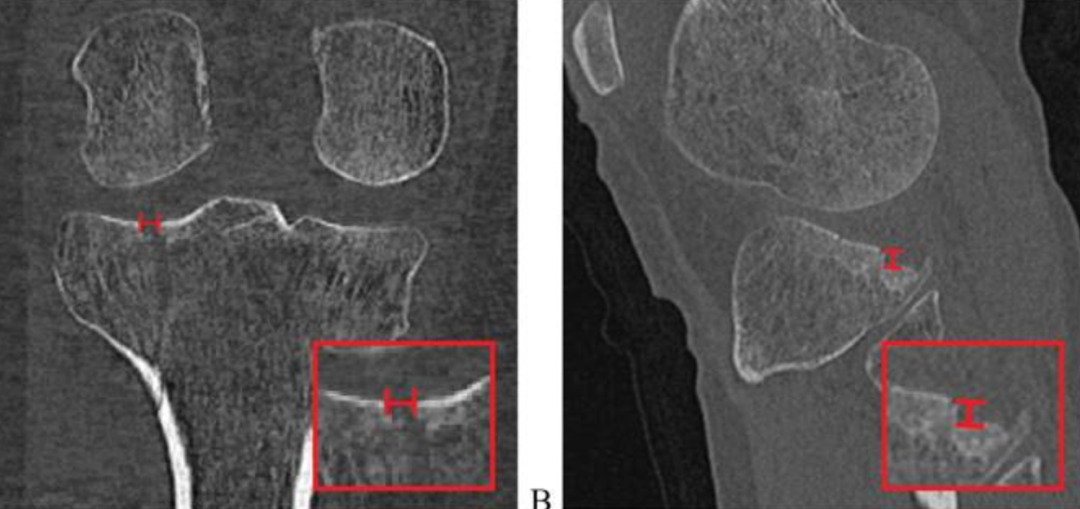

胫骨平台后倾角是矢状面上胫骨平台关节面与胫骨干垂线的夹角。根据胫骨平台骨折三维损伤机制分型,屈曲型损伤的胫骨平台后倾角增加,而过伸型损伤的胫骨平台后倾角减小或消失,甚至为负值。后倾角的变化既可能仅局限于内侧或外侧平台,也可能同时累及双侧平台,在骨折复位时要针对性恢复对应平台的后倾角。

一般来说外侧平台后倾角(平均7.5°)稍大于内侧平台后倾角(平均5.2°),而且两膝的内外侧平台后倾角基本对称,因此在术前计划和术中 复位时可以参考健侧膝关节的平台后倾角。